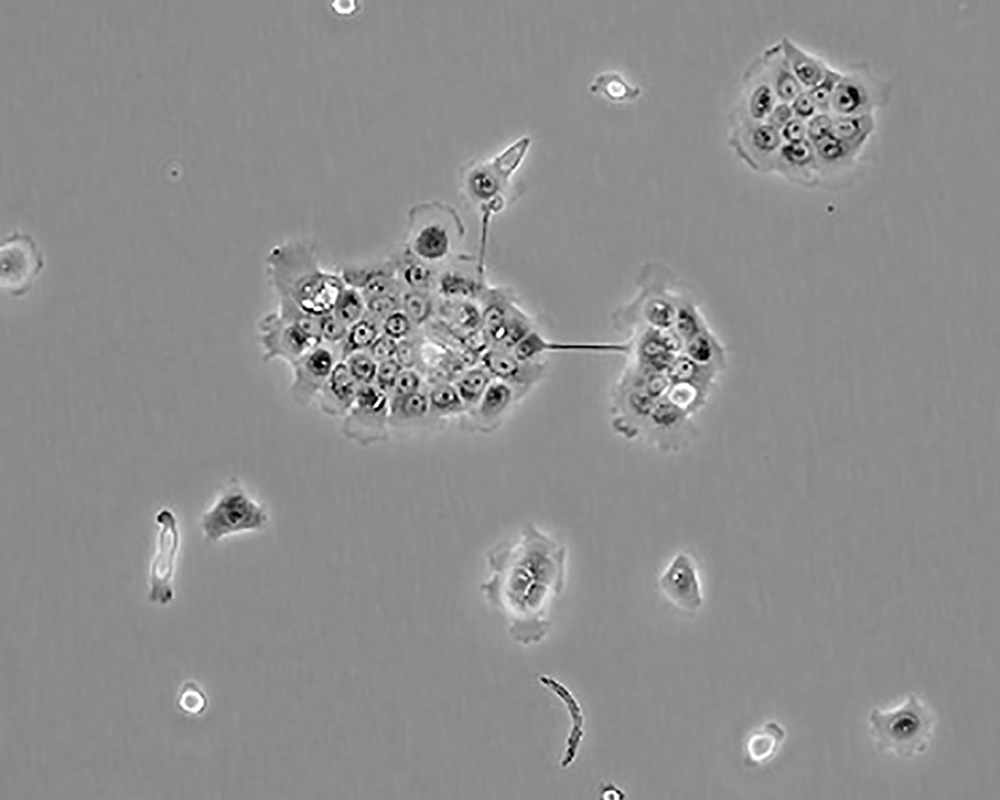

BxPC-3(BxPC3)

產品名稱 BxPC-3(BxPC3)

中文名稱 人原位胰腺腺癌細胞

組織來源 胰腺導管腺癌;女性

形態特征 epithelial

細胞描述 The cells do not express the cystic fibrosis transmembrane conductance regulator(CFTR). A CFTR positive pancreatic line, Capan-1 is available.